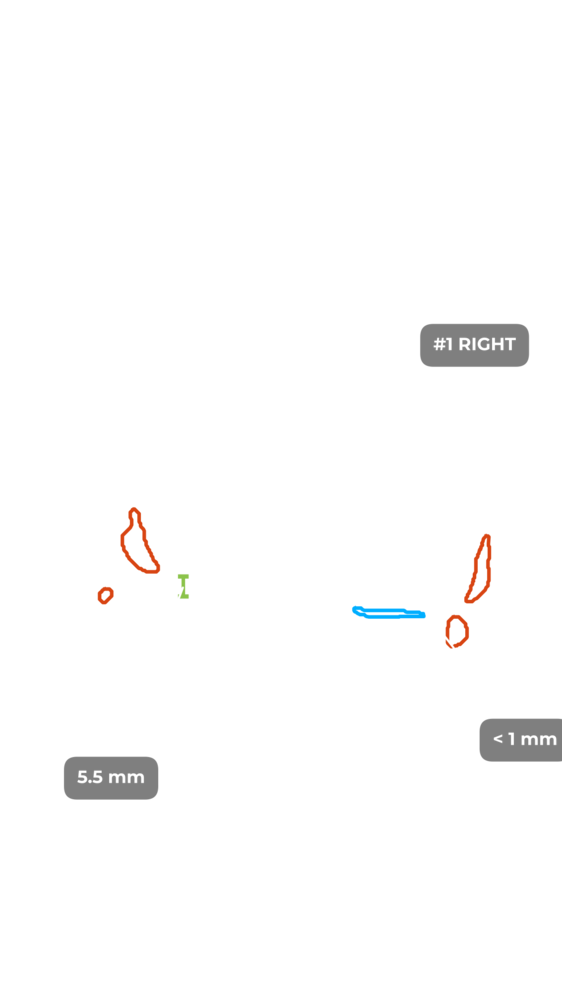

ИИ и алгоритмы интеллектуального анализа для рентгена коленного сустава. Оцените дегенеративные процессы менее чем за 1 минуту